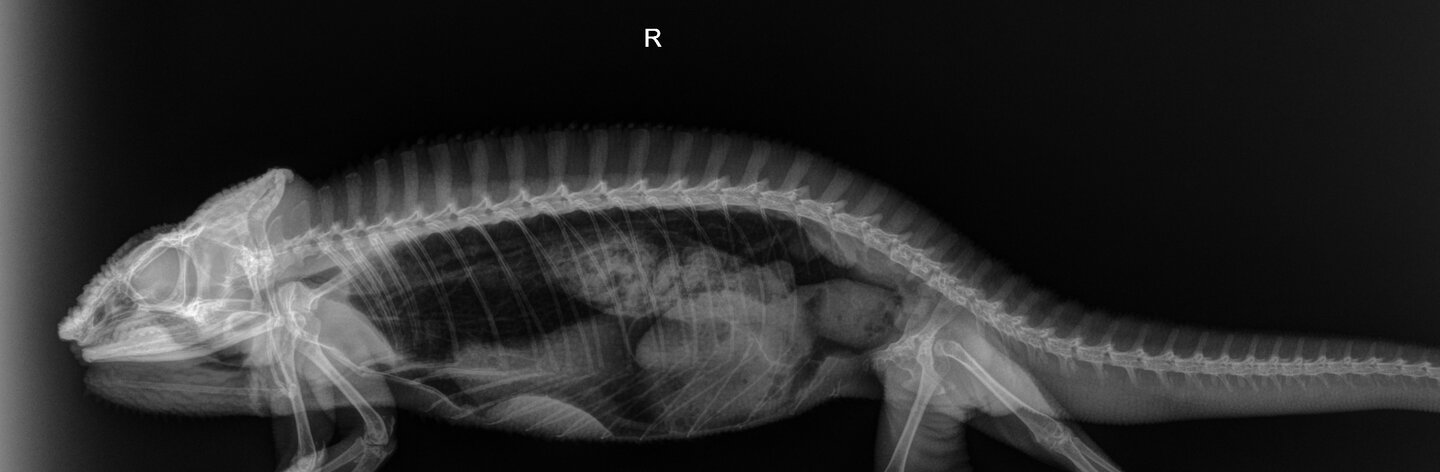

I took him to see Dr. Stein on Saturday at the vet. His X-rays are normal. His blood results showed very elevated Lymphocytes and white blood cells. He is testing for leukemia as well, when he said this I got really freaked out. Do I need to prepare for the worst?